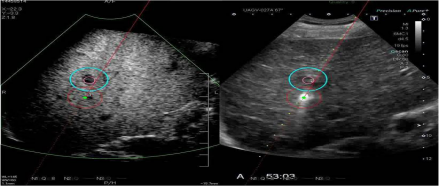

6. 智能融合&智能导航技术(Smart Fusion&Smart Navigation):智能融合技术可实现先前检查所获取的超声容积数据与实时2D超声图像之间的自动位置匹配,可用于介入治疗评估;也有CIVCO omniTRAX装置,实现超声图像和CT/MRI图像之间的自动位置匹配。

智能导航:利使用装有传感器的穿刺针,在超声图像上叠加穿刺针导航引导线,模拟显示穿刺针的路径和针尖的位置来实现导航,实时双屏幕针道显示,临床上利于穿刺介入。